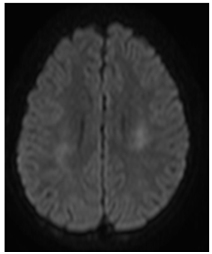

A CT (Computerized Tomography) scan of the skull was requested and did not show any signs of intracranial hemorrhage. Subsequently, magnetic resonance imaging (MRI) of the brain was performed, evidencing two focal areas of high signal in DWI in bilateral centrum semiovale (Figures 1‒5). Considering that the treatment wasn`t finished and still consisted in high and continuous doses of MTX, aminophylline was introduced in order to prevent/reverse the effects of the subacute ischemic event due to the medication.

Figure 1 Focal and symmetrical regions of restricted diffusion on DWI on centrum semiovale.

Figure 4 Focal and symmetrical regions of restricted diffusion on DWI on centrum semiovale.

The imaging modality of choice is MRI, because it has a high sensitivity and specificity for relevant differential diagnosis such as cerebral metastases, opportunistic infection, hemorrhage, dural venous obstruction or ischemic infarction. In acute/subacute stroke like MTX-induced neurotoxicity, DW and T2 hyperintensities are typically located in the periventricular white matter, particularly in the centrum semiovale, and often seen only on DWI (diffusion weighted images).12

The MR imaging findings consists of increased signal intensity on DWI with correlated hypointensity on the ADC map are indicative diminished random water motion, usually associated with irreversible cytotoxic injury. However, it can be identified in acute MTX neurotoxicity related to cytotoxic edema and is not necessarily associated with irreversible cell death as the proposed mechanism. After recovery, DWI findings are usually normal, but T2 and/or FLAIR (Fluid-attenuated inversion recovery) may show residual abnormalities until 3weeks. Reversibility of markedly decreased in apparent diffusion coeficient (ADC) values without a clinically apparent permanent deficit is in striking contrast with findings in acute ischemia.13